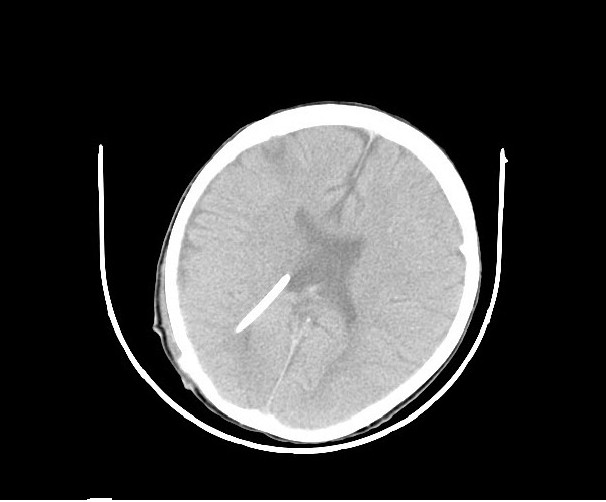

The patient had a fast and uncomplicated recovery, and was discharged 72 h later. A CT scan of the head 8 hours after surgery indicated definitely that the ventricular catheter was located satisfactorily and the hydrocephalus had been resolved (Figure 5).